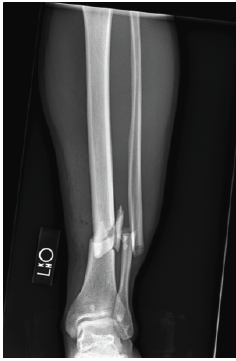

Open Reduction and Treatment with Bone Morphogenetic Protein-2 for Correction of Closed Tibial Pseudoarthrosis in a 32-Year-Old Non-smoking Male with Osteoporosis and Hypogonadism: A Case Report

Samantha Hill , Katherine Slack , Frankie Perry , Kanwar Parhar , Miguel Schmitz

………………………………p.128-132